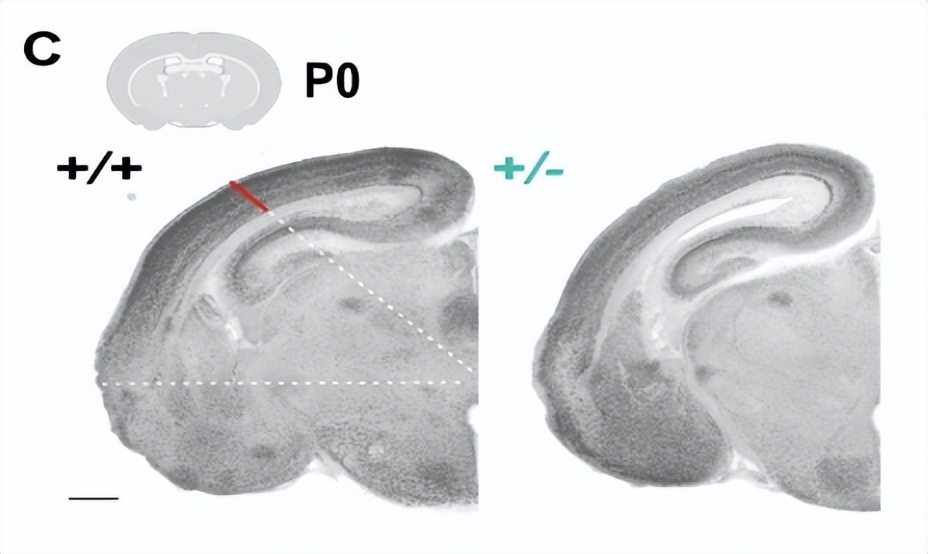

1. MYT1L基因突变的小鼠大脑皮层变薄,脑重量下降,这种大脑结构异常,可能解释一些患者的大脑畸形。

蓝色代表基因突变小鼠的皮质切面图